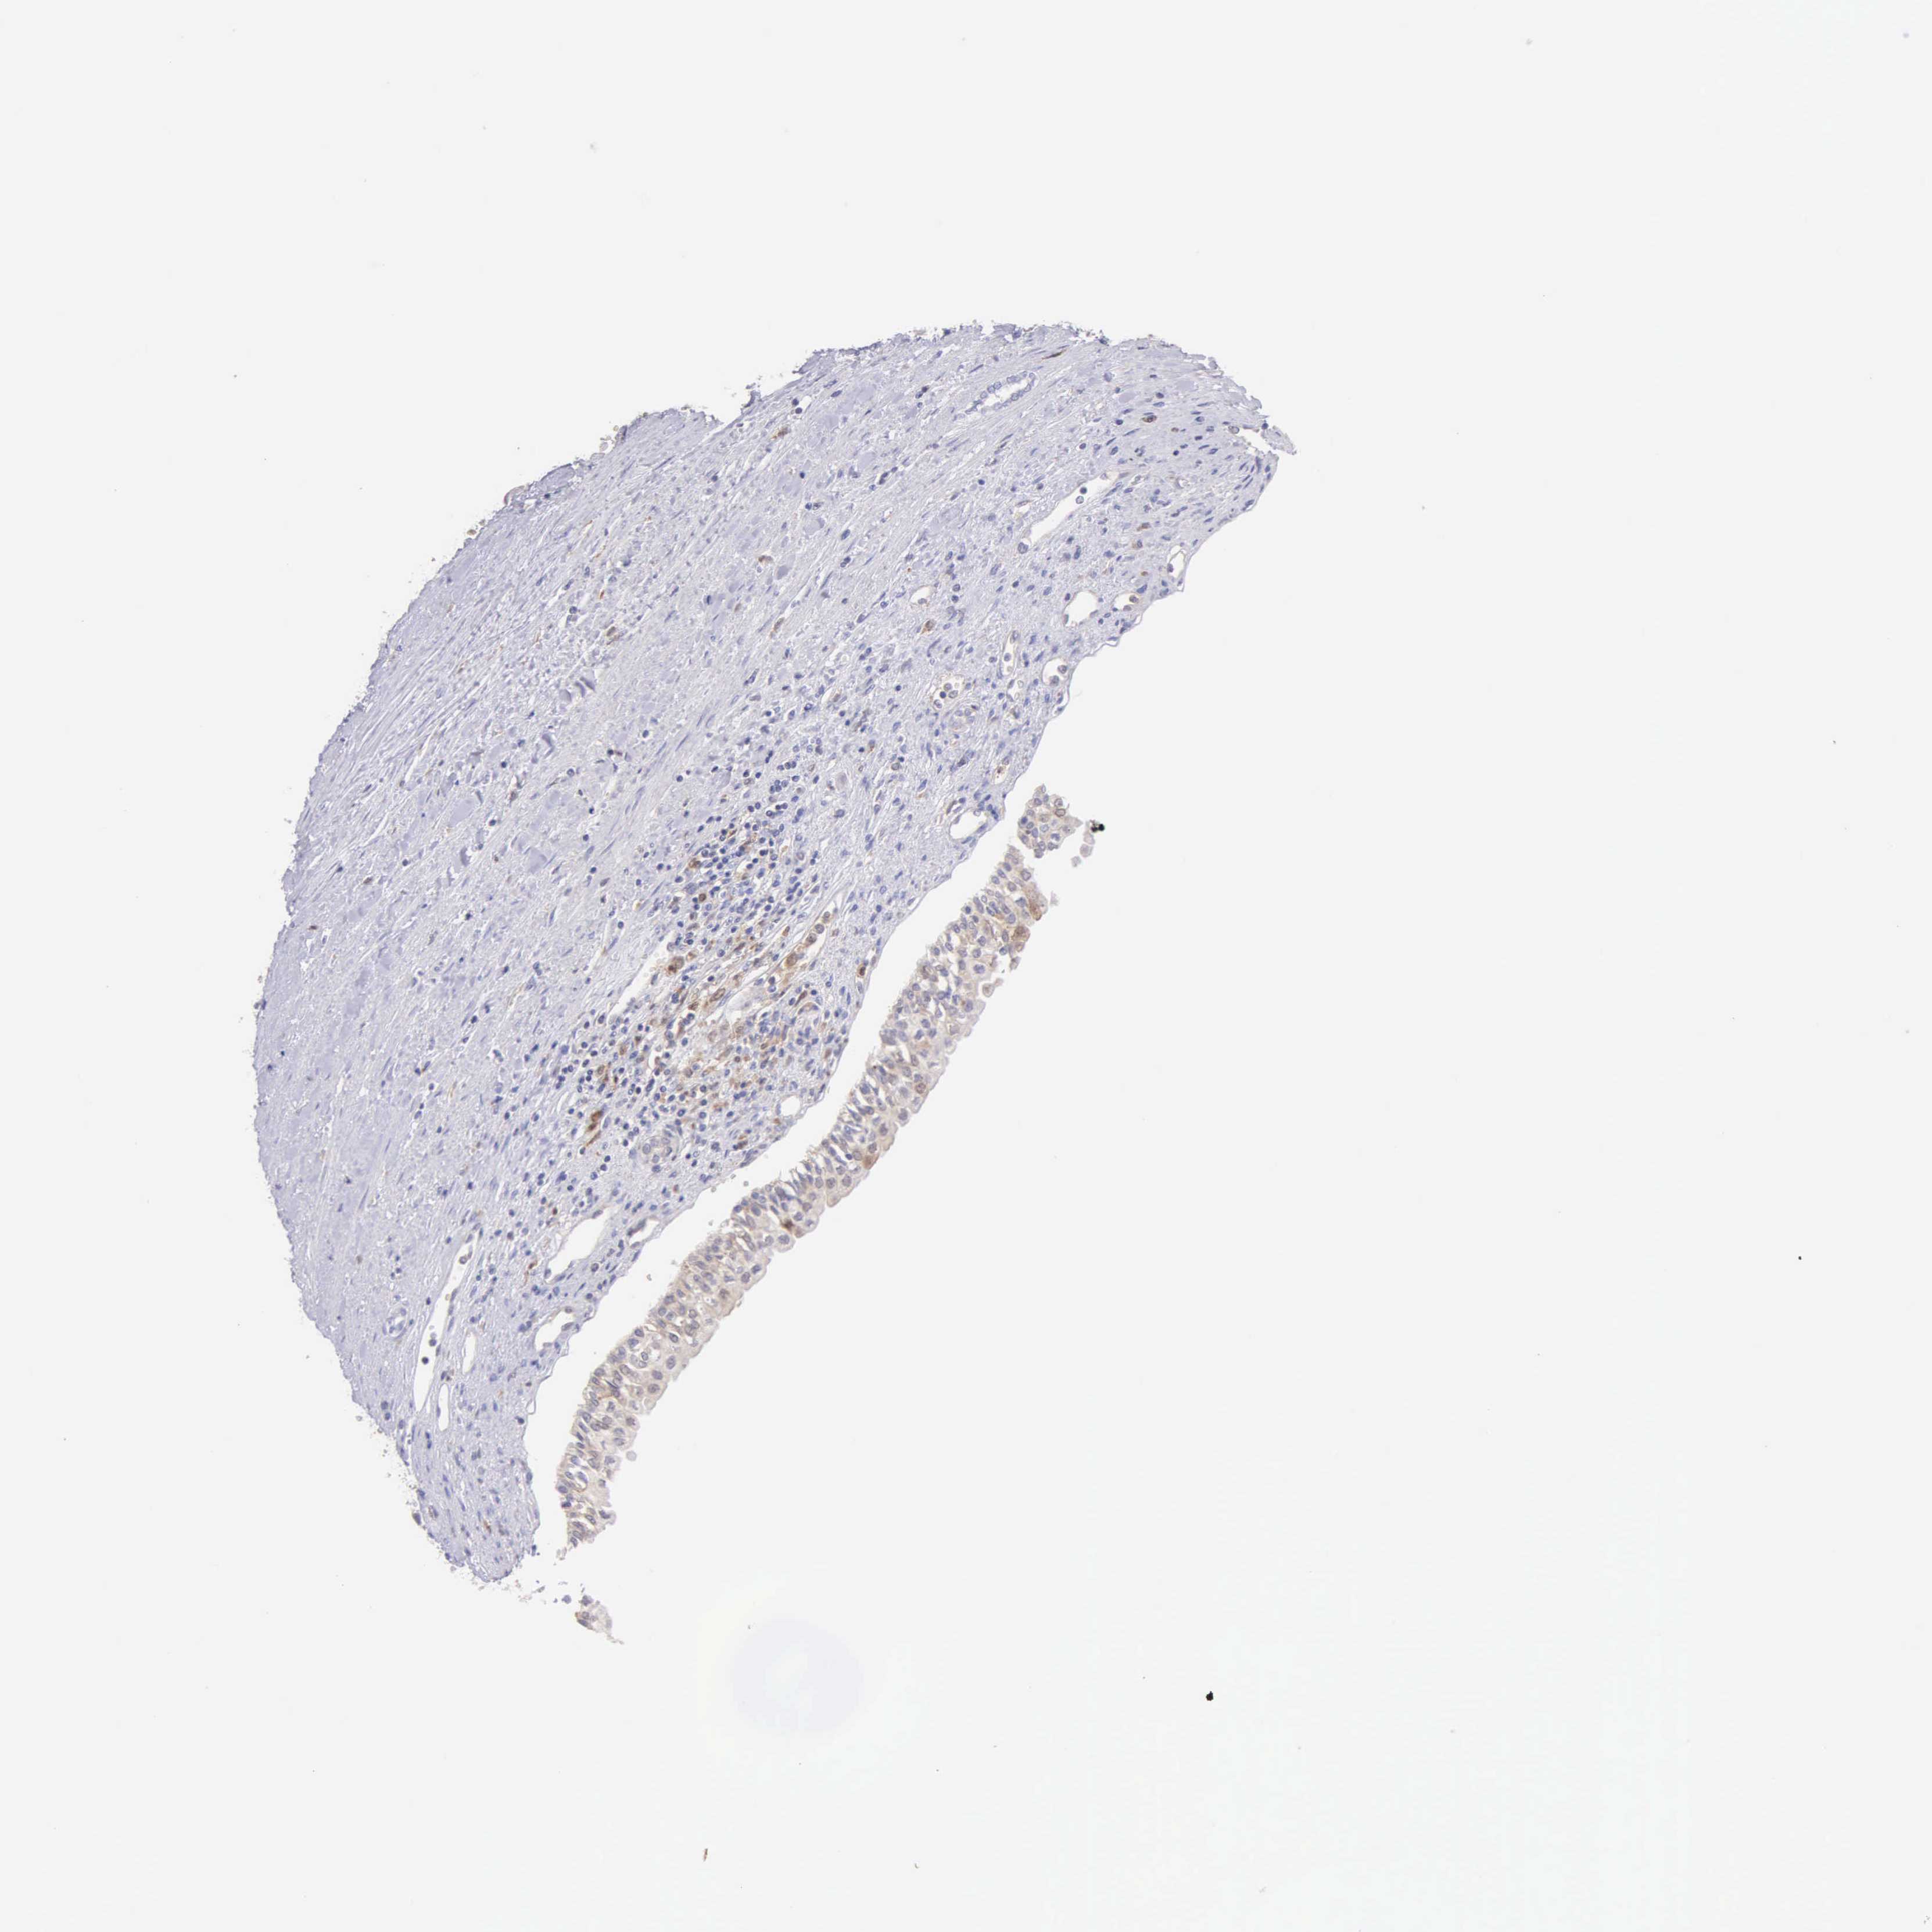

KIDNEY RENAL CLEAR CELL CARCINOMA (VALIDATION) - Interactive survival scatter ploti

The Survival Scatter plot shows the clinical status (i.e. dead or alive) for all individuals in the patient cohort, based on the same data that underlies the corresponding Kaplan-Meier plots. Patients that are alive at last time for follow-up are shown in blue and patients who have died during the study are shown in red.

The x-axis shows the expression levels (FPKM) of the investigated gene in the tumor tissue at the time of diagnosis. The y-axis shows the follow-up time after diagnosis (years). Both axes are complimented with kernel density curves demonstrating the data density over the axes. The top density plot shows the expression levels (FPKM) distribution among dead (red) and alive patients (blue). The right density plot shows the data density of the survived years of dead patients with high and low expression levels respectively, stratified using the cutoff indicated by the vertical dashed line through the Survival Scatter plot. This cutoff is automatically defined based on the FPKM cutoff that minimizes the p-score. The cutoff can be changed by dragging the vertical line or by entering a cutoff value in the square labeled "Current cut-off".

Under the Survival Scatter plot the p-score landscape (black curve; left axis) is shown together with dead median separation (red curve; right axis). Dead median separation is the difference in median mRNA expression between patients who have died with high and low expression, respectively. It is calculated as follows: median FPKM expression of dead patients with high expression - median FPKM expression of dead patients with low expression. This is intended to aid the user in visually exploring custom cutoffs and the associated p-scores and dead median separation.

Individual patient data is displayed and can be filtered by clicking on one or more of the category buttons on the top of the page. Categories describing expression level and patient information include: high, low, alive, dead, female, male and tumor stages. The scale of the x-axis can be toggled between linear and log-scale by clicking on the "x log" button. Mouse-over function shows TCGA ID, patient information and mRNA expression (FPKM) for each patient.

& Survival analysisi

Kaplan-Meier plots summarize results from analysis of correlation between mRNA expression level and patient survival. Patients were divided based on level of expression into one of the two groups "low" (under cut off) or "high" (over cut off). X-axis shows time for survival (years) and y-axis shows the probability of survival, where 1.0 corresponds to 100 percent.

BID is not prognostic in Kidney Renal Clear Cell Carcinoma (validation)

Best expression cut offi

: 31.38

Average pTPM 25.6

Number of samples 100